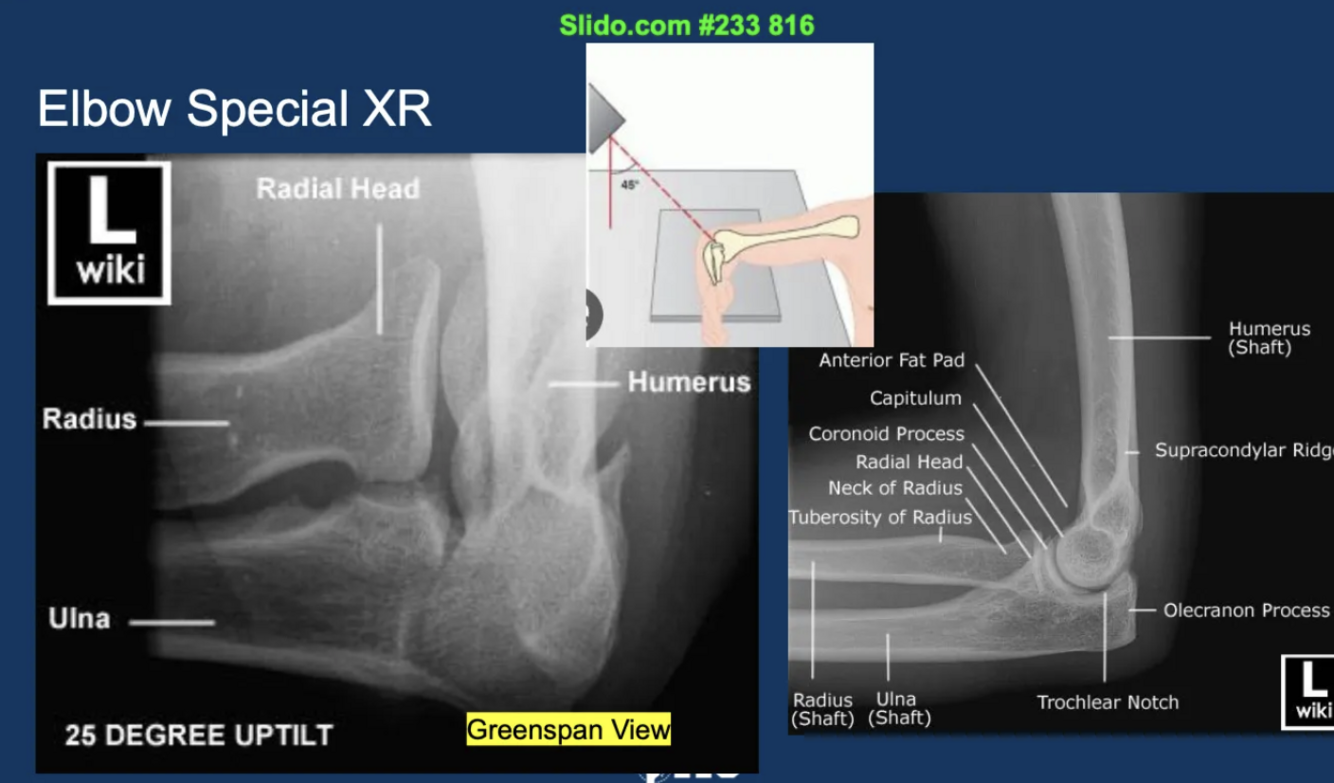

What elbow XR view do we use to visualise radial head fractures?

A

greenspan view